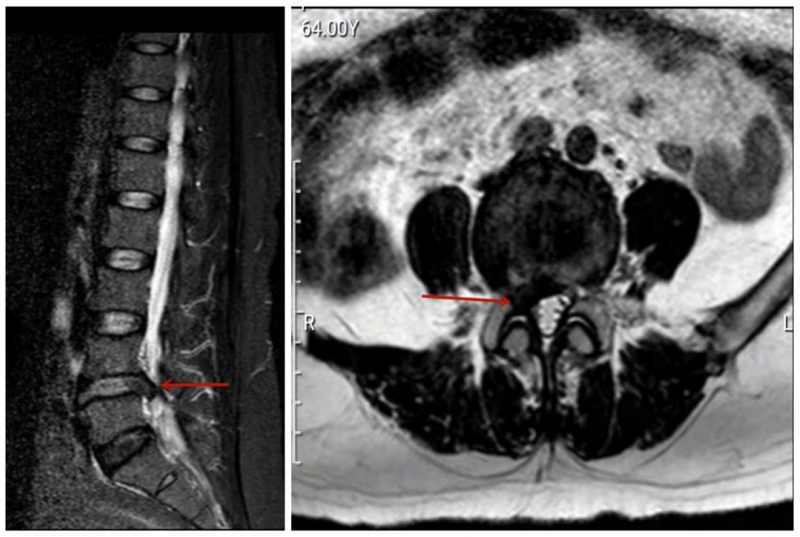

患者的术前核磁检查。